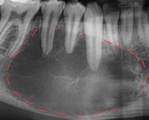

De las 50 radiografías analizadas, 20 pacientes presentaron algún tipo de lesiones periapicales (tabla 1) dentro de los cuales se obtuvieron diagnósticos diferenciales de 3 osteítis condensante, 3 hipercementosis, 3 osteoesclerosis, 4 quiste radicular, 2 quiste dentígero, 1 odontoma, 1 folículo dentario, 2 displasia, 2 granuloma, 1 queratoquiste odontogénico

Se obtuvieron mayores porcentajes en los quistes radiculares (22%), seguidos por un 13% en osteítis, osteoesclerosis, hipercementosis, un 9% en granuloma, displasia y dentígero y en un menor porcentaje con un 4% en queratoquistes, folículo dentario y odontoma. (Gráfica 1)

De las 40 radiografías analizadas, 20 pacientes presentaron lesiones periapicales (tabla 1), se obtuvieron diagnósticos diferenciales de 3 osteítis condensante, 3 hipercementosis, 3 osteoesclerosis, 4 quiste radicular, 2 quiste dentígero, 1 odontoma, 1 folículo dentario, 2 displasia, 2 granuloma, 1 queratoquiste odontogénico. De acuerdo con estos resultados de las radiografías panorámicas examinadas, se pudo encontrar tumores odontogénicos benignos, quistes odontogénicos y alteraciones óseas.

El análisis imagenológico de las 40 radiografías periapicales reveló que el 50% de los pacientes presentaron algún tipo de lesión periapical. Las patologías más prevalentes fueron el quiste radicular (22%) y las alteraciones óseas como la osteítis condensante, la hipercementosis y la osteoesclerosis, con un (13%) cada una. Otras lesiones detectadas incluyeron patologías menos frecuentes como el odontoma y el queratoquiste.

Según la literatura y la comparación del análisis referente a nuestra muestra de estudio podemos decir que la Facultad de odontología-Universidad de Panamá maneja pacientes con una predominación de lesiones periapicales de tipo “quistes odontogénicos” (7 casos, siendo un 35%) como lo son el quiste radicular, dentígero y queratoquiste odontogénico. Por otro lado, también se encuentra una mayor prevalencia en alteraciones óseas (9 casos, siendo un 45%), tales como la osteítis condensante, osteoesclerosis y la hipercementosis. Cabe destacar que este tipo de lesiones pueden ser encontradas en todo tipo de pacientes, independientemente, de su edad, género o raza.